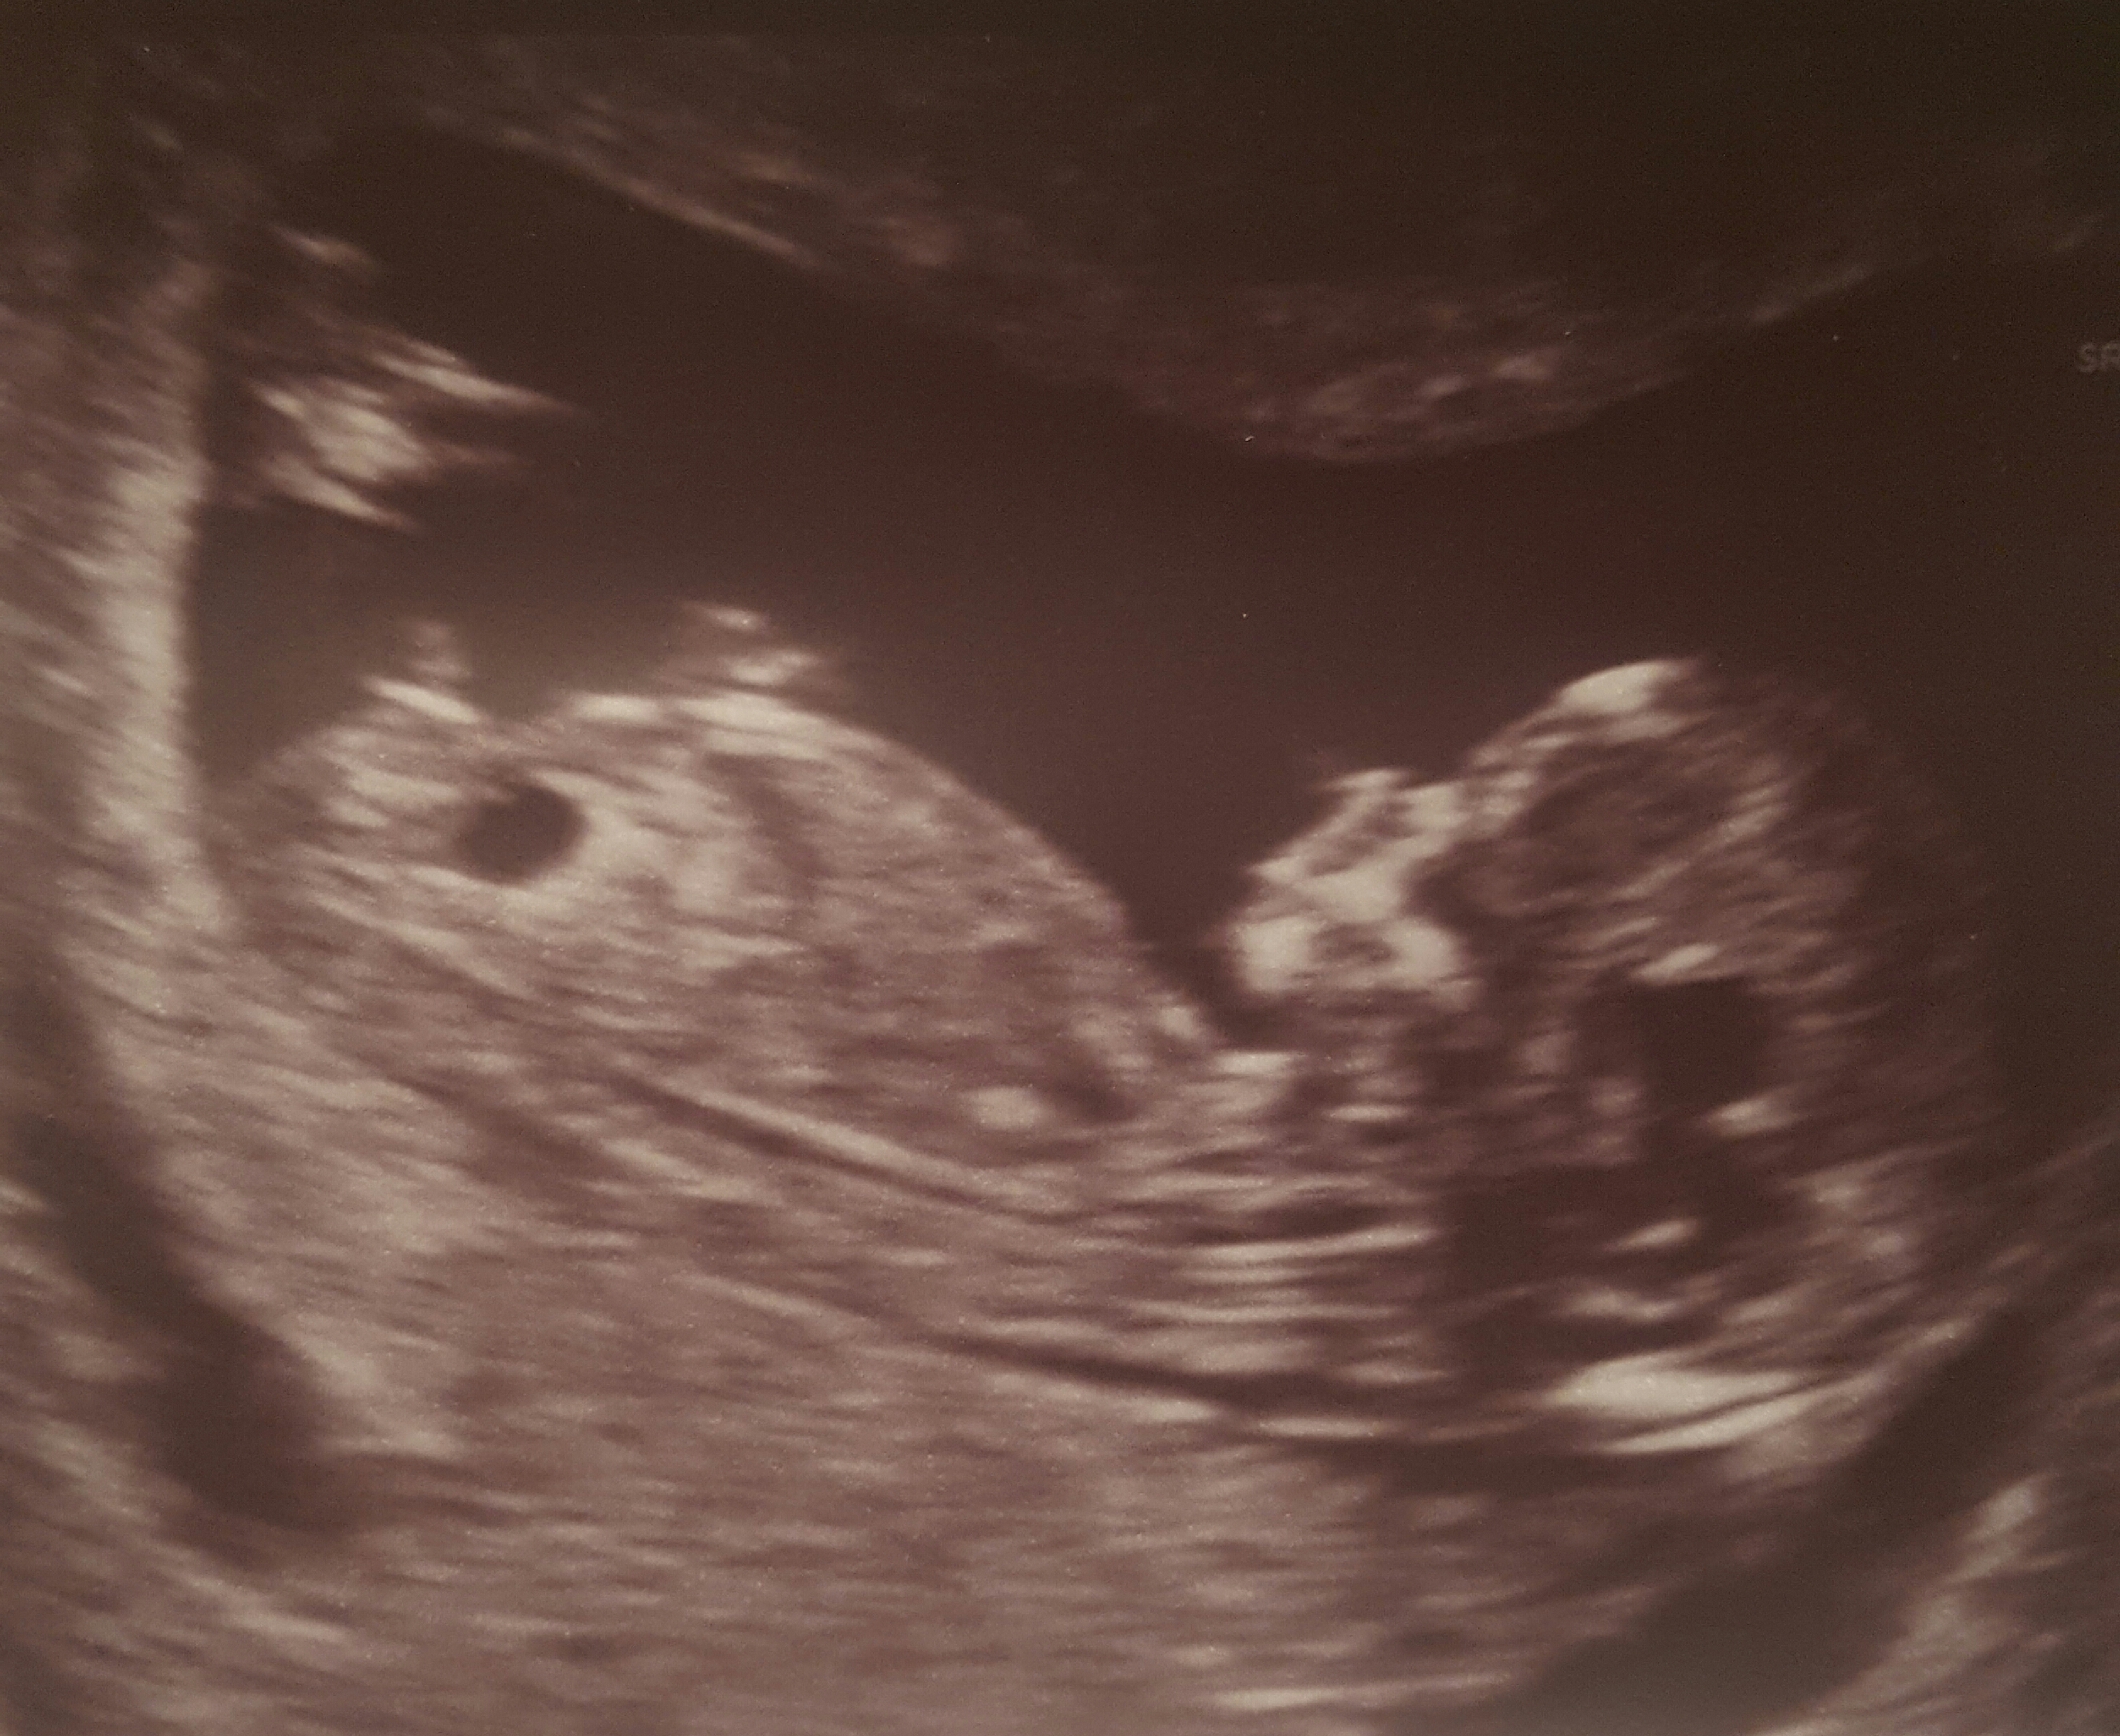

This is my 12+4. I have my 20 wk scan at end of February, but have been trying to guess before!

I have searched nuby shots and think it may be girly? But really not sure so any guesses appreciated